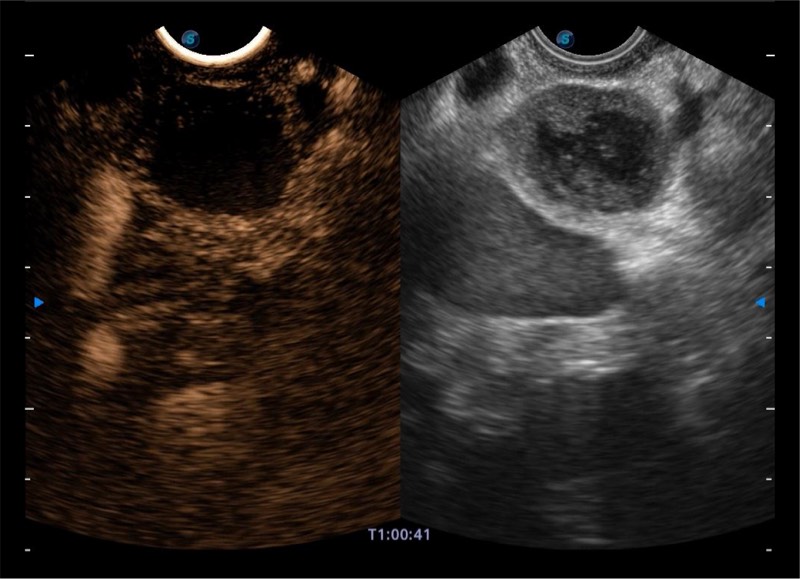

搭载百万级CMOS成像技术

及自主研发凸阵换能器,

可呈现优质的内镜和超声画面

基于二十年的超声技术积累,云顶集团官网提供了最新一代的独立超声主机,在提供高质量图像的同时满足多学科使用。具备常见多普勒技术并提供弹性成像、声学造影等高端影像技术。新一代传感器具有更强的抗干扰能力并减少图像伪影。